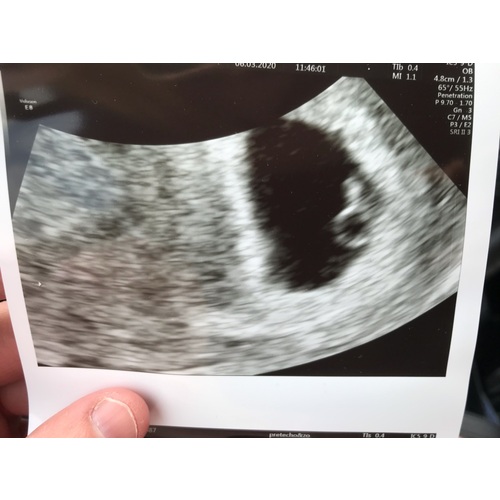

Ik heb mijn eerste echo gehad in het zh tussen de 5 a 6w ivm eerdere eug en miskramen dit was inwendig ze konden zien dat het gelukkig op de goede plek zat en zagen heeelll klein een hartslag toen nog niet goed te zien hoe ver ik precies was. Vandaag 2de echo gehad en dit was uitwendig en duidelijke hartslag te zien en begin van groei van het brein en ze kon me zeggen dat ik vandaag 7w4d was 🥰. Succes!

5+6 kloppend hartje toen ook gezien helaas met 7 weken een miskraam 😢 maar hoop dat je aan de echo zelf iets heb 😘